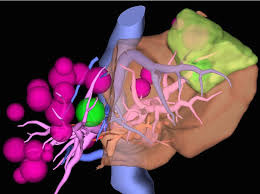

※ 진단 당시

- 간 전체에 30개 이상 전이 병변

- 가장 큰 병변도 명확하게 관찰

- 수술·국소치료 불가능 판정

※ 선택한 치료

- αGalcer 수지상세포 백신 치료

- NKT 3종 복합 면역세포 치료

- 소량의 면역 항암제(옵디보 + 여보이) 병용

※ 복합 면역세포치료 1사이클(7회) 후 CT 결과

- 간에 보이던 대부분의 전이 병변이 소실

- 최대 직경이었던 전이 병변도 뚜렷한 축소

- 영상상 명확한 종양 신호 감소 확인

이는 단순한 “안정화” 수준이 아니라,

종양 자체가 면역 반응에 의해 제거된 전형적인 패턴에 해당합니다.

- αGalcer 백신 → 암세포를 정확히 인식하도록 면역 시스템을 교육

- NKT 3종 복합 면역세포 → 공격력이 높은 3종의 면역 세포를 동시 투

- 소량의 면역 항암제(옵디보 + 여보이) 병용 요법

이 세 가지가 동시에 작동하면서

“내 몸의 면역이 암을 제대로 인식하고, 끝까지 제거하는 구조”가 만들어진 것입니다.